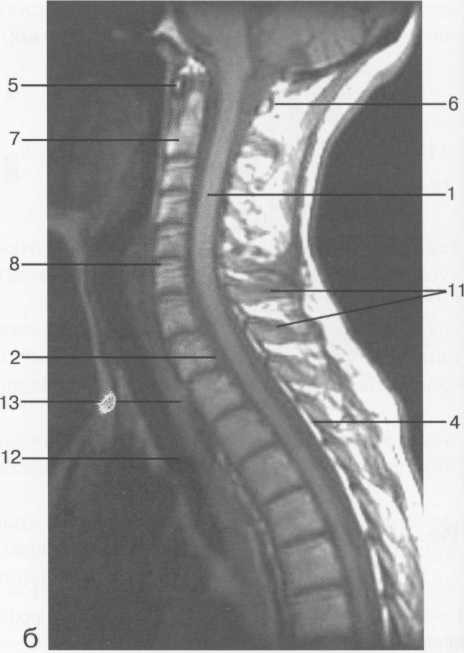

МРТ исследования дают широкую возможность исследовать  все структуры спинного мозга в разных плоскостях. ( рис. 37-41 )

Рис. 38. МРТ. Срединное сагиттальное изображение шейного отдела позвоночника.

а-Т2-ВИ;б-Т1-ВИ.

1 -- спинной мозг; 2 -- субарахноидальное пространство; 3 -- дуральный мешок (задняя стенка); 4 -- эпидуральное пространство; 5 -- передняя дуга С1; 6 -- задняя дуга С1; 7 -- тело С2; 8 -- межпозвонко­вый диск; 9 -- гиалиновая пластинка; 10 -- артефакт изображения; 11 -- остистые отростки позвонков; 12 -- трахея; 13 -- пищевод.